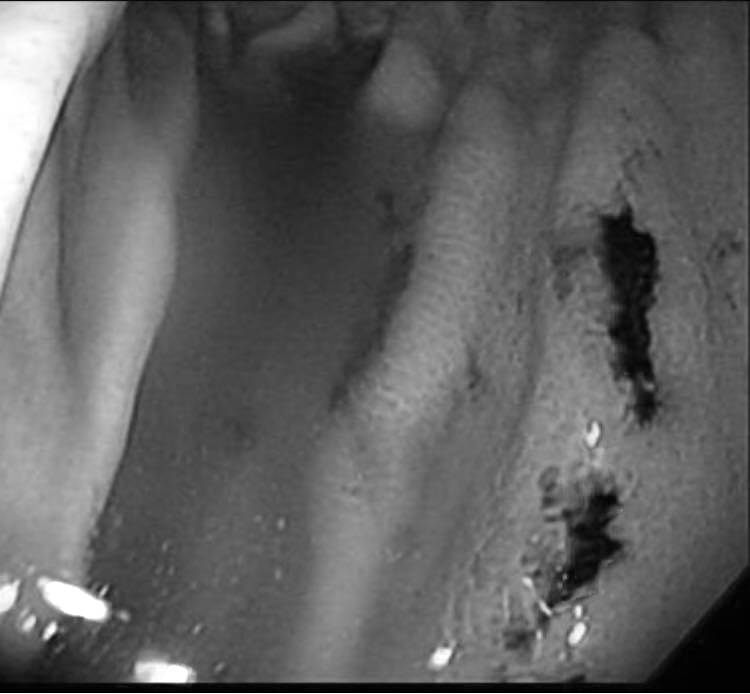

▲黑色處為出血痕跡,翻攝自臉書 (錢政弘 胃腸肝膽科醫師) ,下同。

40多歲男病患因為左上腹悶痛、最近常解出深色便便就醫,錢醫師一照胃鏡驚覺「胃裡有大大小小共5處潰瘍和糜爛,還有出血過的痕跡」,但男病患對上述5大成因卻矢口否認。男病患性格開朗也沒吃藥,「平常飲食清淡,三餐正常,不吃甜食或零食,也不喝咖啡茶或果汁,檢查也沒有幽門桿菌」。錢醫師刨根究底才得知,原來男病患近日買了一箱可樂,每晚在家喝1罐。